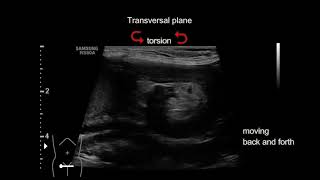

Uterine torsion in a dog video

Uterine torsion in a dog

Uterine torsion in a dog